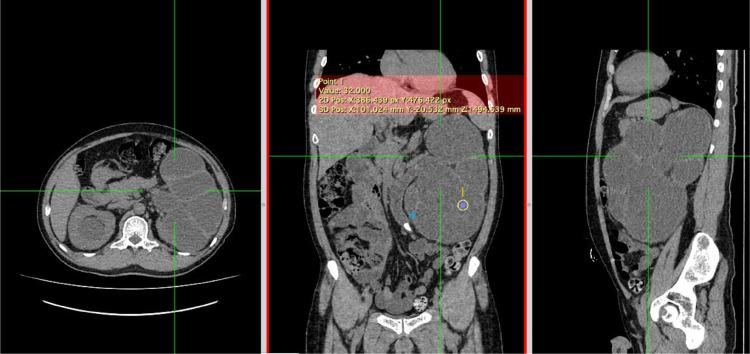

Pyonephrosis is hydronephrosis accompanied by a bacterial infection in the kidney, causing suppurative destruction of the renal parenchyma; this condition is an emergency and usually associated with stones or chronic urinary tract infections. Urinalysis is typically inaccurate for establishing the diagnosis, as bacteriuria may not manifest due to ureteral obstruction. We reported a 55-year-old male patient with flanks pain and an account of stone expulsion. Based on history taking, physical examination, radiology examinations, and percutaneous nephrotomy, we concluded a diagnosis of pyonephrosis causing by as known as Group B Streptococcus. While both US and CT scan guided the early diagnosis, CT was more accurate as it is able to capture the renal function and the underlying cause of obstruction. Pyonephrosis was described as having a pus collection in the pelvicalyceal system, cortex thinning, and the appearance of stones. Pyonephrosis is a rare emergency, and many clinicians find it challenging to recognize since the presentations are frequently nonspecific. In order to prevent renal failure and the spread of bacteremia that entails life-threatening urosepsis, acquiring imaging knowledge (sonography and CT) and other findings are indispensable in determining this entity.